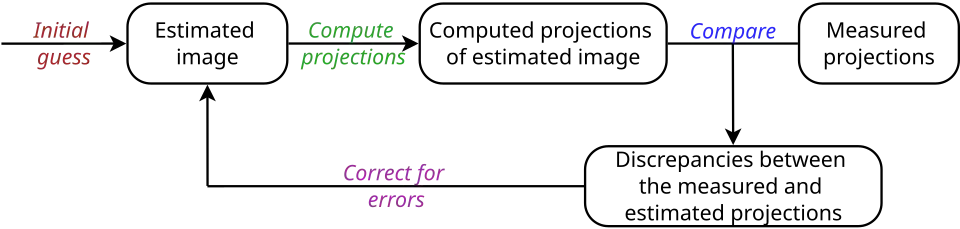

Note that can account for noise, acquisition geometry, etc. The Fly Algorithm is an example of iterative reconstruction. Iterative methods in tomographic reconstruction are relatively easy to model:

where is an estimate of , that minimises an error metrics (here ℓ2-norm, but other error metrics could be used) between and . Note that a regularisation term can be introduced to prevent overfitting and to smooth noise whilst preserving edges. Iterative methods can be implemented as follows:

(i) The reconstruction starts using an initial estimate of the image (generally a constant image), (ii) Projection data is computed from this image, (iii) The estimated projections are compared with the measured projections, (iv) Corrections are made to correct the estimated image, and (v) The algorithm iterates until convergence of the estimated and measured projection sets.